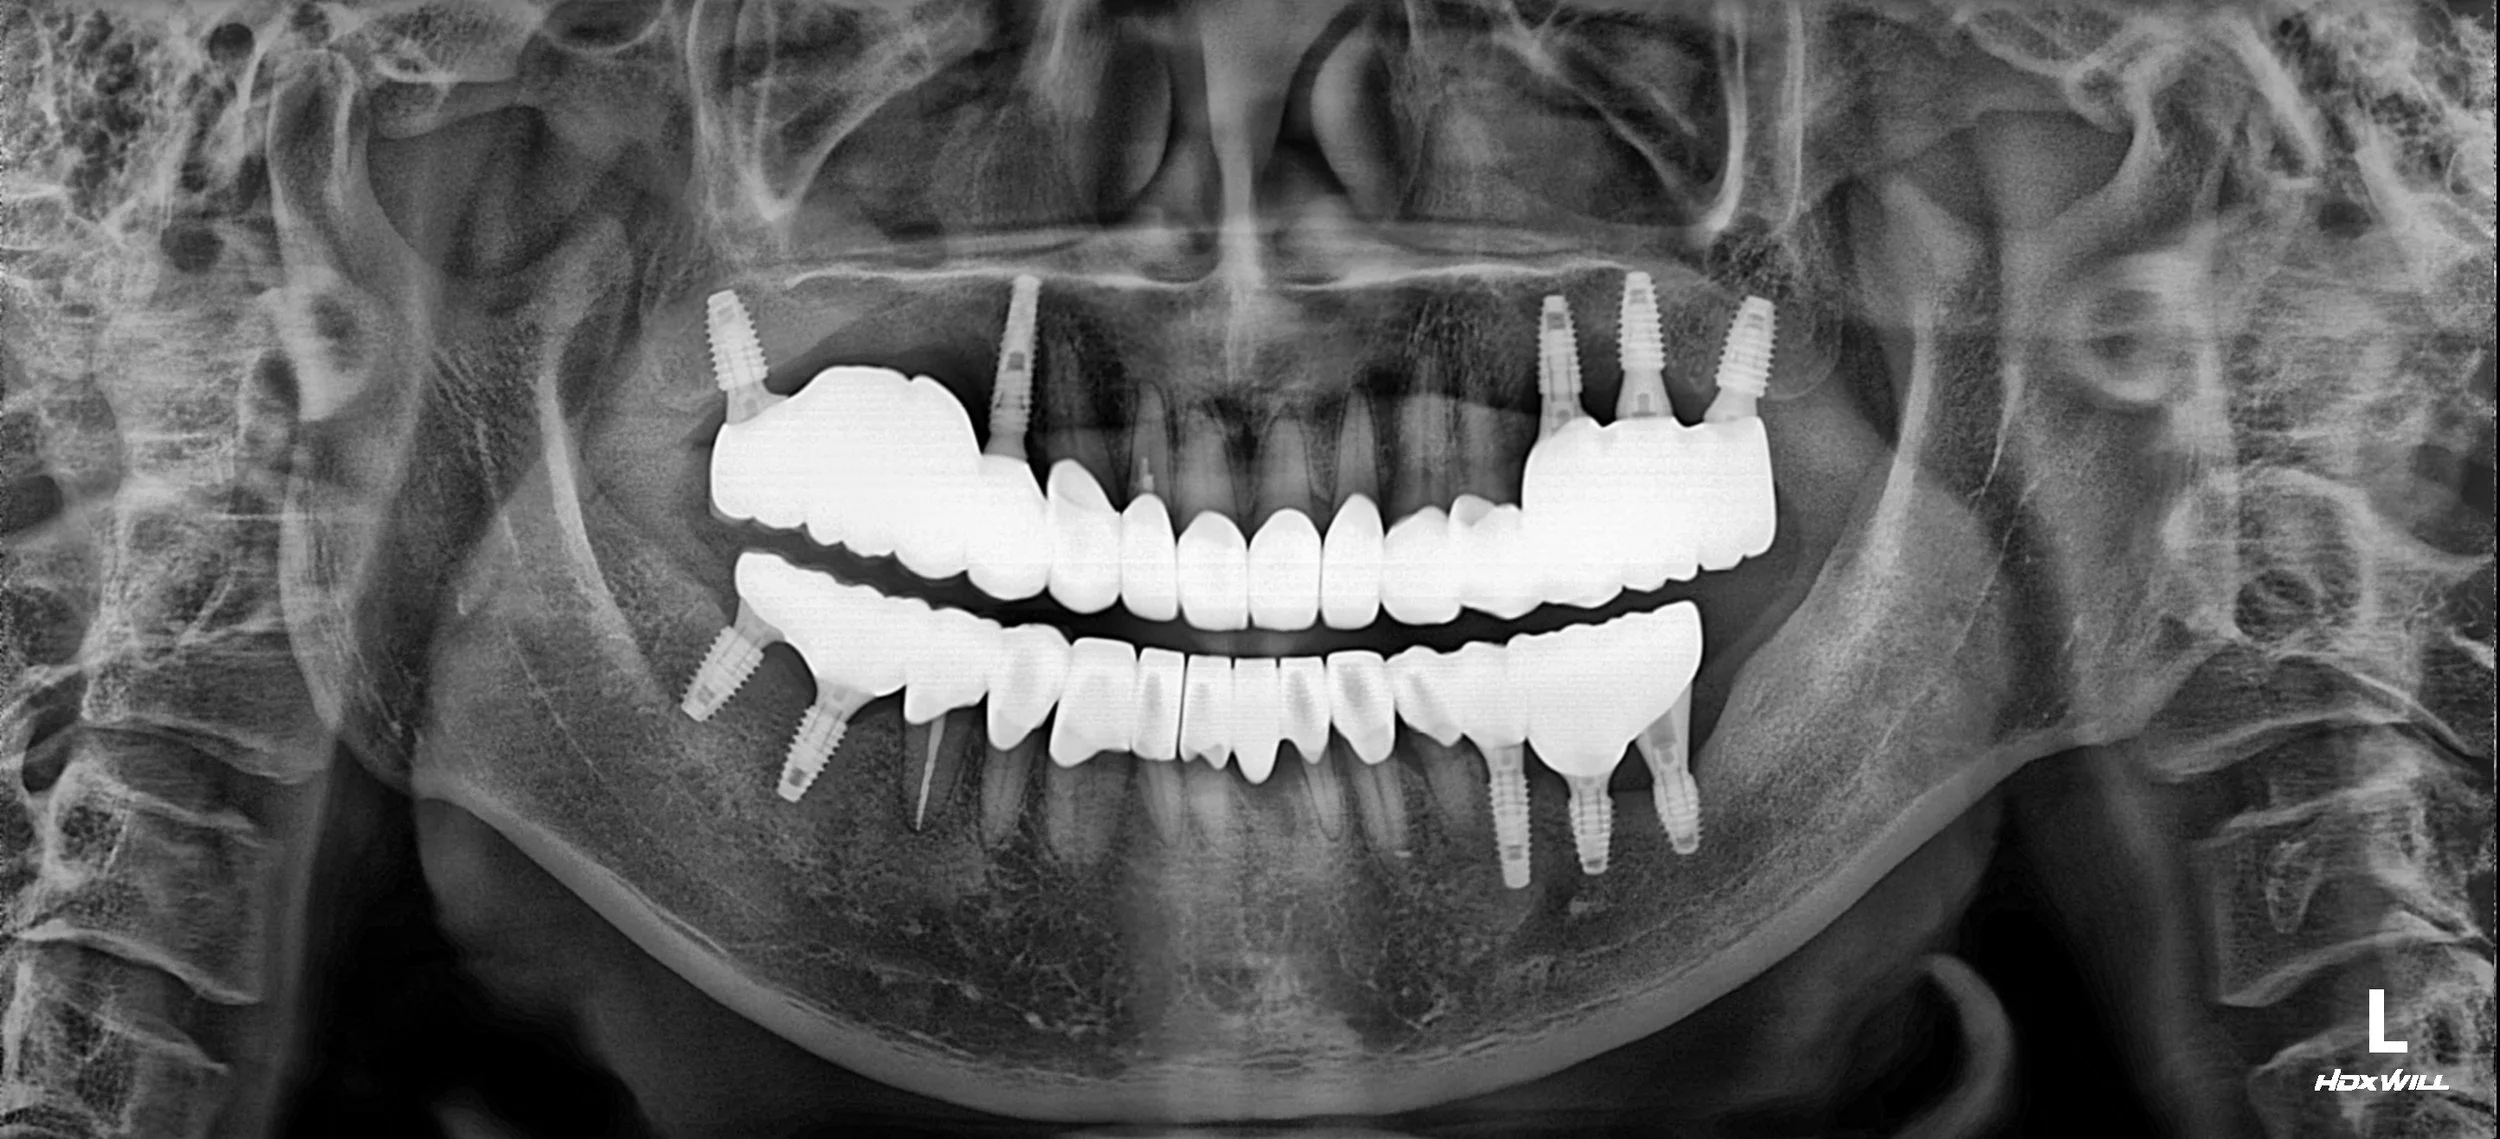

3. Implant Re-treatment & Functional Integration: Dental implants were strategically re-placed in the posterior segments at the intended new VDO. This phase was meticulously planned to prevent future overloading and to harmonize with the new mandibular position.

4. Final Prosthetic Phasing: definitivo definitive anterior porcelain bridges and crowns were delivered for aesthetic rejuvenation. Simultaneously, the final posterior implant-supported bridges were finalized at the stable VDO, ensuring a sustainable and functional result.

The final result is a transformative improvement, moving from the discomfort of iatrogenic failure and skeletal collapse to a stable, functional, and symmetrical Fixed Rehabilitation.